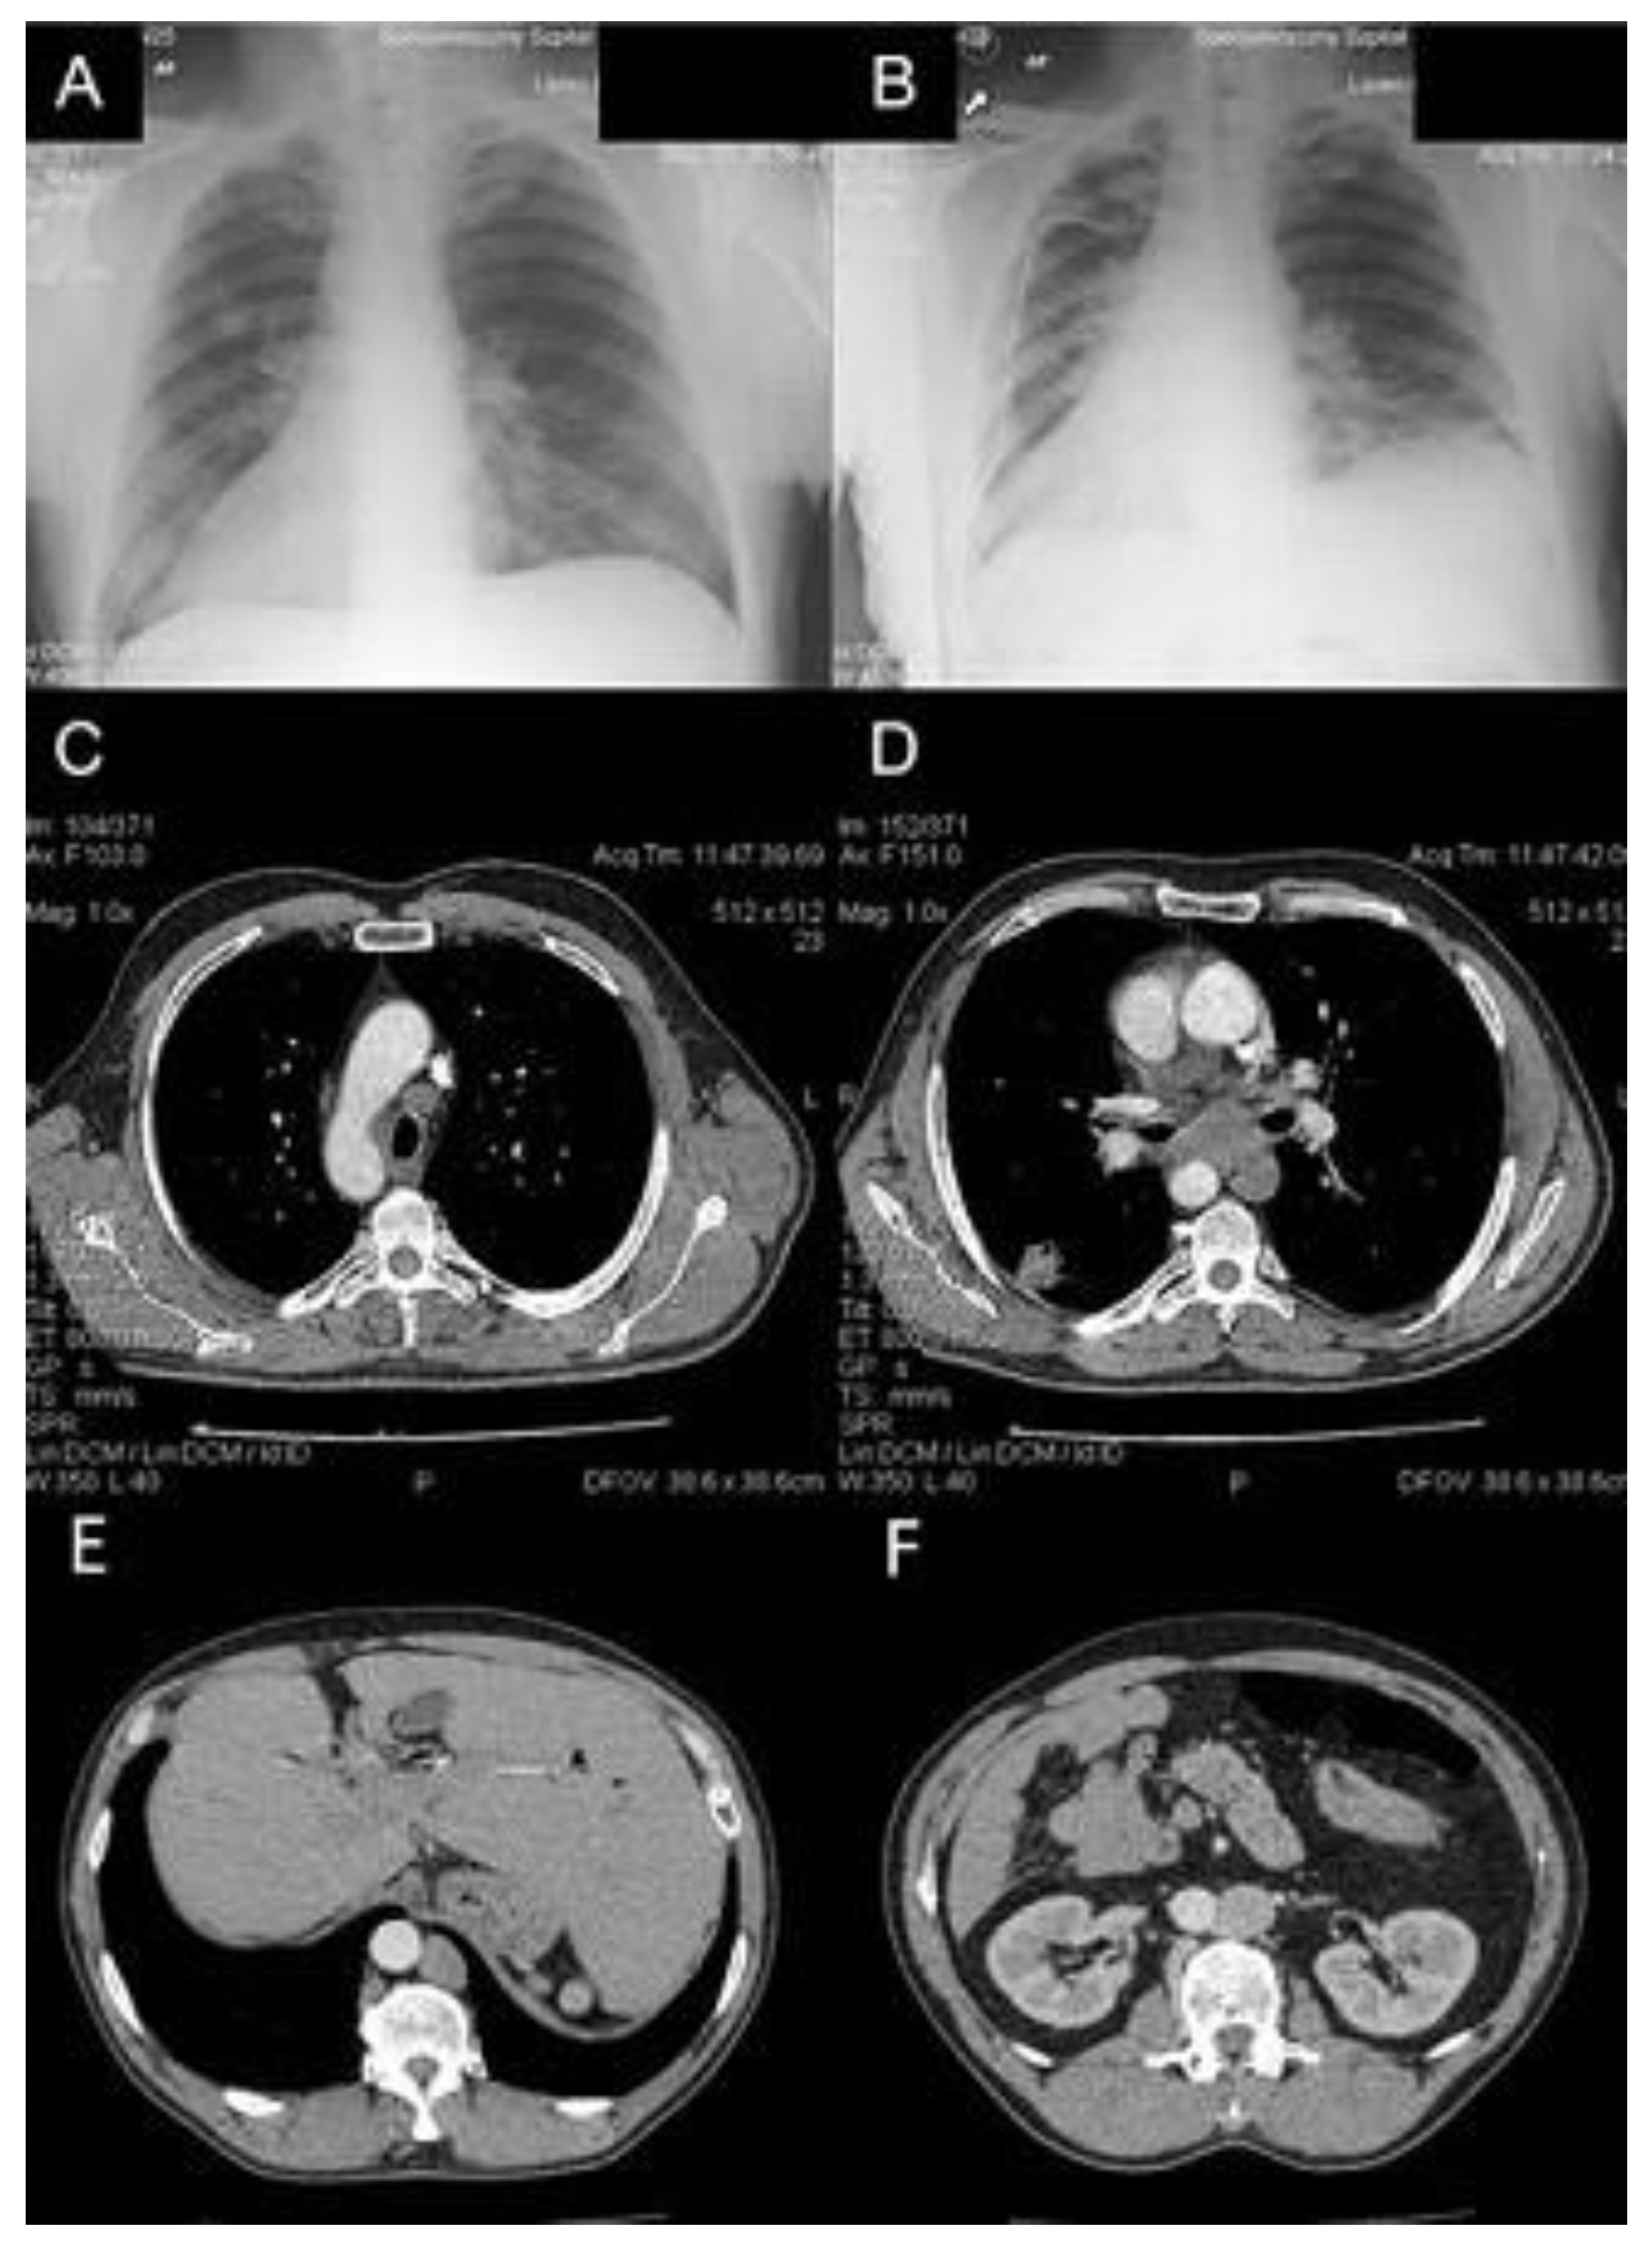

A 56-year-old man with previously confirmed SIT was admitted to the Thoracic Surgery and Transplantation Department in January 2014 due to a 2.5 cm tumor of unknown etiology in the right lung, detected in a chest X-ray. The patient did not present any clinical symptoms. The image of SIT was confirmed in a contrast-enhanced chest computed tomography (CT). In addition, CT confirmed a 28 × 22 mm tumor in the sixth right segment, with a 9 mm satellite tumor located slightly higher, with enlargement of the mediastinal lymph nodes (Figure 1). Positron emission tomography FDG-PET/CT and endobronchial ultrasound (EBUS) were inaccessible during hospitalization. The diagnosis procedure was extended with an ultrasound fine needle aspiration biopsy of the right lung tumor and left supraclavicular lymph node with a diameter of 6 mm. Lung tumor biopsy was ineffective and cancer cells were not observed in the supraclavicular lymph node biopsy specimen, although the high level of carcinoembryonic antigen CEA (95.3 ng/mL) suggested adenocarcinoma in stage N2. A bronchofiberoscopy showed the right side of the lobar opening segmental bronchi anatomy in a configuration typical of the left lung, and an analogous image on the left side, where the bronchial configuration of the lobar openings’ segmental bronchi anatomy corresponded to the right lung. Subsequently, the patient qualified for surgery via right thoracotomy. Intraoperatively, the correct anatomy of the left lung (bilobar lung) on the right side and the tumor in the sixth segment, corresponding to the chest CT, was found; however, the posterior part of interlobar fissure was undeveloped. The entire anatomy of the mediastinum also corresponded to the left side, including the nodal station of the aorto-pulmonary window. Intraoperative examination confirmed metastases to the nodes of groups 5 and 7 and the procedure was limited to the sixth segmentectomy with mediastinal and lung hilar lymphadenectomy. The surgical technique was based on reconstructing the posterior part of the interlobar fissure by scissor stapling and ligation of the artery and vein to segment VI, followed by the linear stapler resection of segment VI.

Figure 1.

(A,B) Pre- and postoperative chest X-rays of the patient with SIT and lung cancer. (C,D) Chest CT showing rearrangement of mediastinal vessels and 2.5 cm tumor in VI right segment with enlargement of lymph nodes 4R and 7. (E,F) Abdominal CT showing position of the liver on the left side and position of the aorta on the right side.